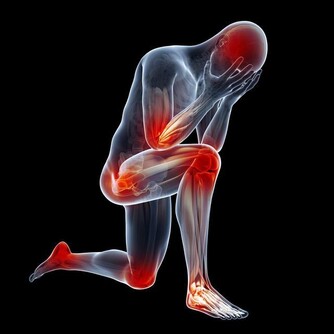

痛風是由單鈉尿酸鹽沉積所致的晶體相關性關節病,與嘌呤代謝紊亂和(或)尿酸排泄減少所致的高尿酸血症直接相關,特指急性特徵性關節炎和慢性痛風石疾病。

主要包括急性發作性關節炎、痛風石形成、痛風石性慢性關節炎、尿酸鹽腎病和尿酸性尿路結石,重者可出現關節殘疾和腎功能不全。

痛風是長期嘌呤代謝障礙,導致體內長期尿酸增高,會在局部形成尿酸結晶,特別是下肢的足背小關節,會導致痛風性關節炎,或是直接形成痛風石,從而會刺激關節面引起反复的疼痛。其臨床特點就是高尿酸血症。但在疼痛急性發作期並不一定的尿酸最高時。